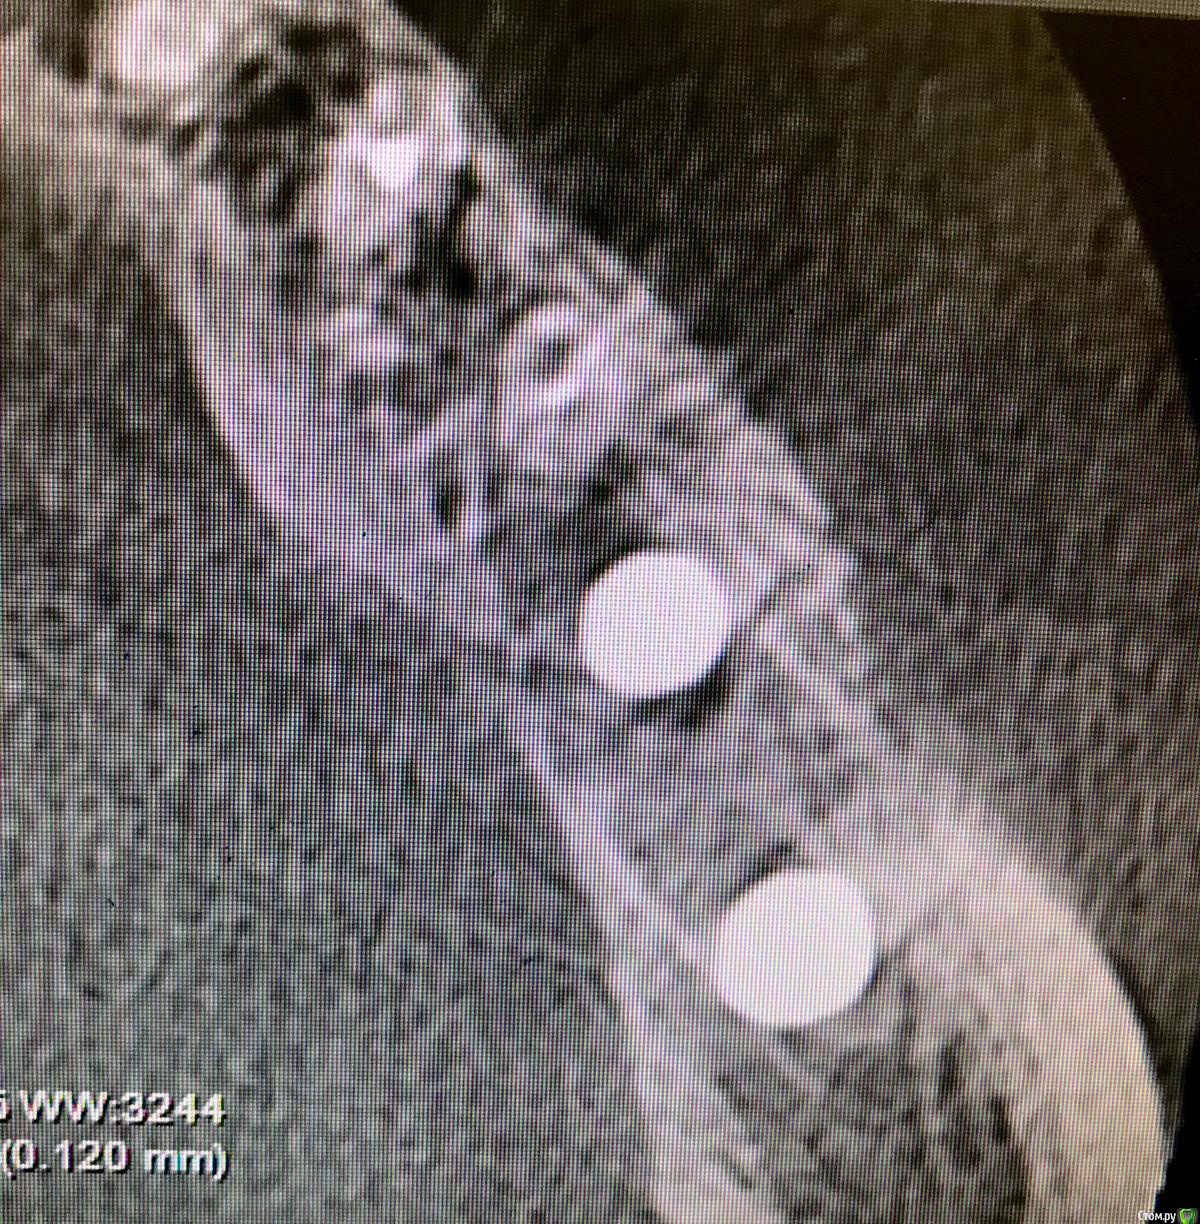

Kostoprav Опубликовано 21 декабря, 2018 Поделиться Опубликовано 21 декабря, 2018 Поделитесь опытом. Какой был графт,какой доступ,условия? На каком этапе заметили неудачу? С чем связываете? Какой срок наблюдения?графт остеобиол+ i prf . доступ аналогичный как у автора темы, использовал данную методику в боковых отделах нижней и верхней челюстях. из 6 пациентов только у двоих я получил прирост и то в одном случае результат был на троечку.неудачу замечал на этапе компьютерной томографии через 6 мес- отсутствие прироста кости либо графт просто "не прирастал" к кости ,а инкапсулировался в слизистой ( кт прилагается ). неудачи связываю с нестабильностью графта и возможно были повреждения периоста при его отслойке как следствие прорастание мягких тканей в графт. Ссылка на комментарий

колесников Опубликовано 22 декабря, 2018 Автор Поделиться Опубликовано 22 декабря, 2018 Я бы не назвал это неудачей,аугментат довольно плотно контактирует с кортикалкой. Мне кажется вы слишком низко отслоились,должна получится округлая сосиска. Я отслаиваю коронально,затем моделирую нужной формы. 1 Ссылка на комментарий